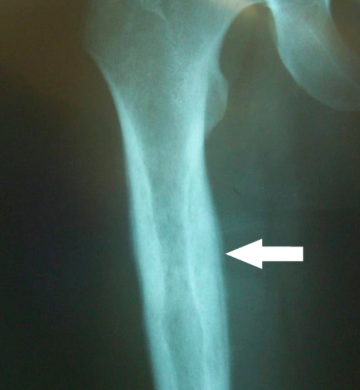

Blount:

A few children with bowlegs, however, continue to progress and worsen, and in some cases the bowing is unilateral. This is termed Blount disease and is characterized by an abnormality in the medial aspect of the proximal tibial epiphysis.

Labs: Radiographically there is a prominent step abnormality with beaking at the proximal tibial epiphysis.

Treatment: Aggressive treatment is essential, as the disease can be rapidly progressive and lead to permanent growth disturbances. Bracing can be effective up to the age of 3; later correction may require surgery. Blount disease can occur in several forms: infantile (ages 1-3 years), juvenile (ages 4-10 years), and adolescent (age 11 years and older). Clinically, the findings are the same; in the adolescent group, radiograph findings are less prominent.